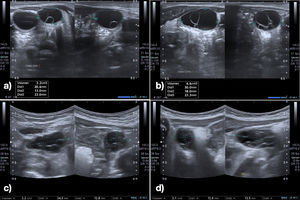

The blood work detected elevation of FSH, LH and estradiol levels (Fig. 2), and the abdominal ultrasound scan revealed ovarian enlargement and cystic lesions (Table 1).

| Left ovary ultrasound (cm3) | 3.2 | 2.2 | Not visualized |

| Right ovary ultrasound (cm3) | 6.6 | 2.1 | Not visualized |